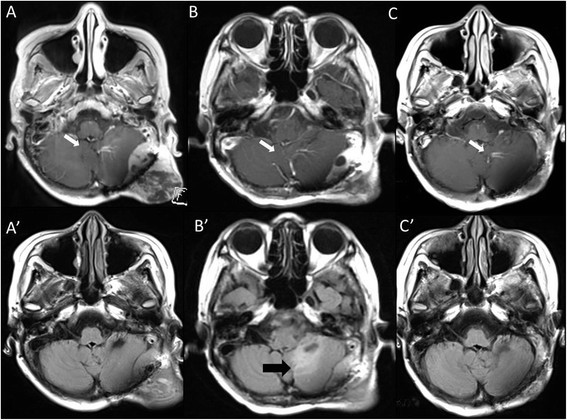

36+ Brain Tumor Growth After Radiation PNG. Patient had visual field deficit which. The brain undergoes ionizing radiation (ir) exposure in many clinical situations, particularly cyst growth is common, unpredictable, and should be followed during and after therapy, because it contributes to late toxicity.

Besides regular physical and neurological exams and blood tests, you may need periodic magnetic resonance imaging. The radiation used to destroy cancer cells can also hurt normal cells in the area that is radiated. Brain tumor cells grow and unlike other normal cells, they don't die.

There are two main types of tumors: The following list includes some of the most common side effects of radiation therapy for brain tumors. A brain tumor is an abnormal growth of tissue in the brain or central spine that can disrupt proper brain function. The least aggressive type of brain tumor is often.